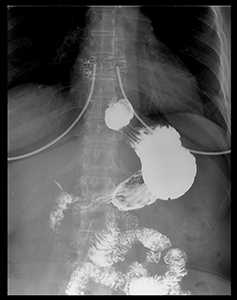

Контрастной рентгенографией, или рентгеном желудка с барием, называют метод обследования, который позволяет получить серию подробных изображений внутреннего строения органов пищеварения.

С помощью обследования специалист получает данные о размере, форме и структуре желудка. Поскольку обычный рентген не позволяет сделать четкое изображение мягких тканей и полости желудка, для получения подробных снимков применяется контрастное вещество - сернистый барий. При рентгене желудка с барием врач может оценить динамику заполнения органа, что показывает норму или патологию его моторной функции.

Обнаружение в органе злокачественного процесса

При подозрении на развитие злокачественного процесса рентген желудка с барием рекомендуется делать в обязательном порядке, так как последствия недуга могут быть смертельно опасны для пациента. На снимках раковый процесс выглядит как дефект слизистой оболочки. Часто после рентгена желудка с барием выполняется эндоскопическое исследование, и отбирается образец новообразования для лабораторного исследования.

Если рентген желудка с барием проведен правильно и с должной подготовкой пациента, обследование может дать достаточно исчерпывающей информации для постановки диагноза в большинстве случаев. При этом для обнаружения того или иного заболевания специалист оценивает ряд параметров.

Нарушения просвета желудка

Нарушения просвета желудка могут говорить о развитии злокачественного процесса либо о дивертикулезе. Если на рентгене желудка с барием просвет сужен, возможен диффузный фибропластический рак. При дивертикулезе на рентгене желудка с барием просвет выглядит большим, чем должен быть в норме.

Симптом ниши

Нишей называют тень контрастной массы, которая заполняет дефект при язве или развитии злокачественного процесса. В зависимости от расположения дефекта, на рентгене желудка с барием различают контурную и рельефную нишу. В первом случае силуэт дефекта виден анфас, во втором - в профиль.

Недостаток наполнения виден на снимке в виде темной области

Темная область на рентгене желудка с барием говорит о наличии места, в которое контраст не смог попасть. Как правило, это случается при атрофическом гастрите или опухоли.